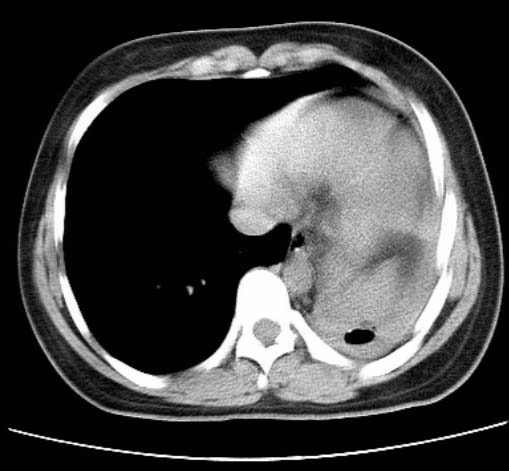

标题: CT25648:求教:是肺发育不全还是结核?

女  20岁。一月前咳血,诊“肺结核”抗痨治疗一月后,咳血停止,现复查。病人精神好。前后ct片对比未见明显变化。既往体检“正常”

1)考虑左肺结核并肺不张、支气管扩张。2)纵隔疝。

考虑左肺结核,左肺毁损,纵膈左偏,既往体检正常不可靠,tb一个月也不会这个样子的,有钙化,应该病程较长,冰冻三尺非一日之寒!

左肺发育不全。

结核,左肺毁损。